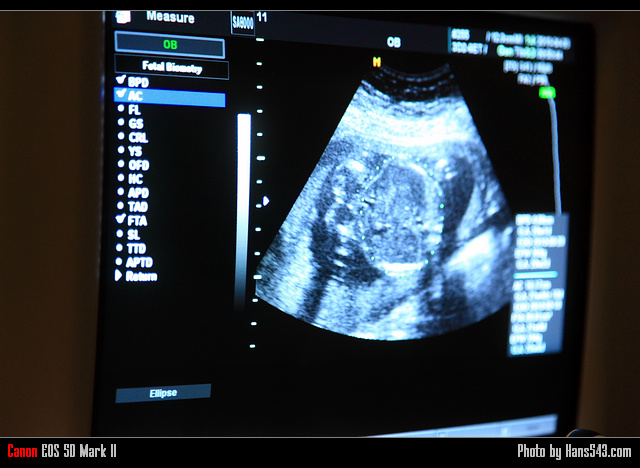

這是爸比第一次幫妳拍照喔~

家中的新成員:小公主.Q比(同時也是新女王…Orz)八月就要來報到了,

利用這次產檢的機會,帶著相機去幫Q比好好拍拍^^

翰斯第一次帶相機去拍照,Q比已經20週大囉~

現在的婦產科,配備都非常先進,

現在的週數已經可以幫忙數手、腳趾頭的數目是否有異常,心跳聲是否正常,嘴唇是否正常,以及看到各種身體的比例喔~

這是Q比小公主的頭圍,是個頭圍正常的健康寶寶喔~

這是Q比小公主的肚圍,據說有21週的水準(其他身體器官都才20週),

其實對著螢幕拍並不好拍,

因為對著CRT螢幕拍照,會有一道一道的黑色橫紋,會影響成像,

另外,因為環境很黑,所以翰斯用最大的光圈來拍,

但是因為是在側邊角度拍照,所以可能會有左邊對到焦、右邊對不到焦的狀況…

這是Q比的腿,

綠色測量線標示的是Q比的腿骨,醫師說,Q比是個長腿妹喔~

這是Q比的背面,很清楚的可以看到脊椎的影像,